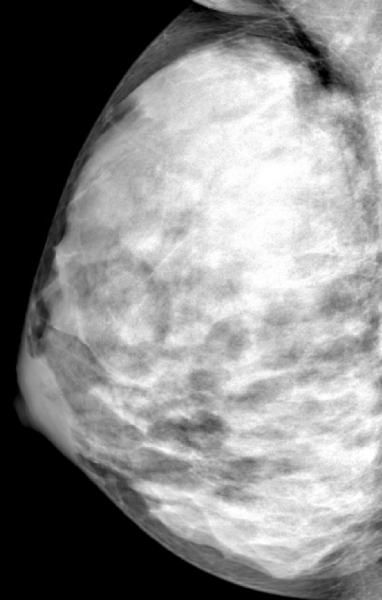

Breast density is already known to be a strong and independent risk factor for breast cancer. The American Cancer Society (ACS) considers women with extremely dense breasts to be at moderately increased risk of cancer and recommends they talk with their doctors about adding magnetic resonance imaging (MRI) screening to their yearly mammograms.

Breast cancer patients showed higher mammographic density than healthy participants up to the age of 50. The healthy controls demonstrated a significant decline in density with age following a linear pattern, while there was considerably more variability in density regression among the breast cancer patients.

"The results are interesting, because there would appear to be some form of different biological density mechanism for normal breasts compared to breasts with cancer, and this appears to be most obvious for younger women," said Perry. "This is not likely to diminish the current ACS guidelines in any way, but it might add a new facet regarding the possibility of an early mammogram to establish an obvious risk factor, which may then lead to enhanced screening for those women with the densest breasts."